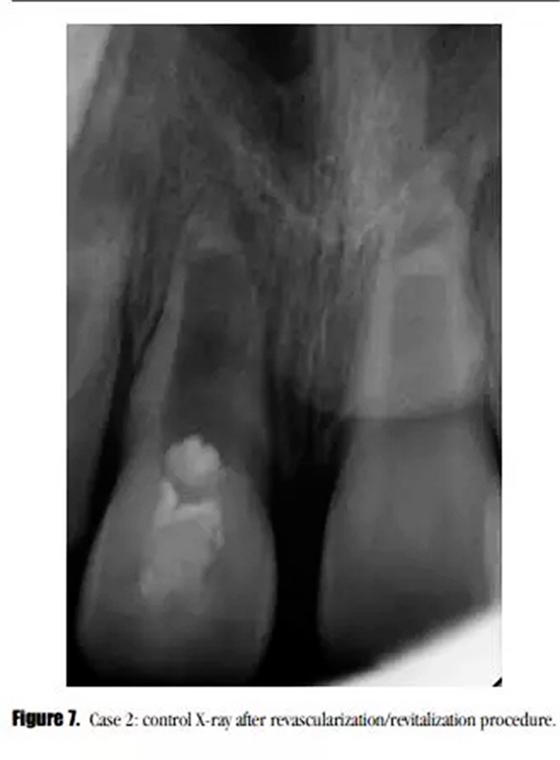

采用與之前所述一致的方法對患牙進行治療,患者癥狀消失。在初次就診之后的3個月后,我們開始了第二次治療。術(shù)后X線顯示,牙根進一步發(fā)育,沒有牙根根管壁的沉積,MTA塌陷進入到血凝塊中。(圖7)